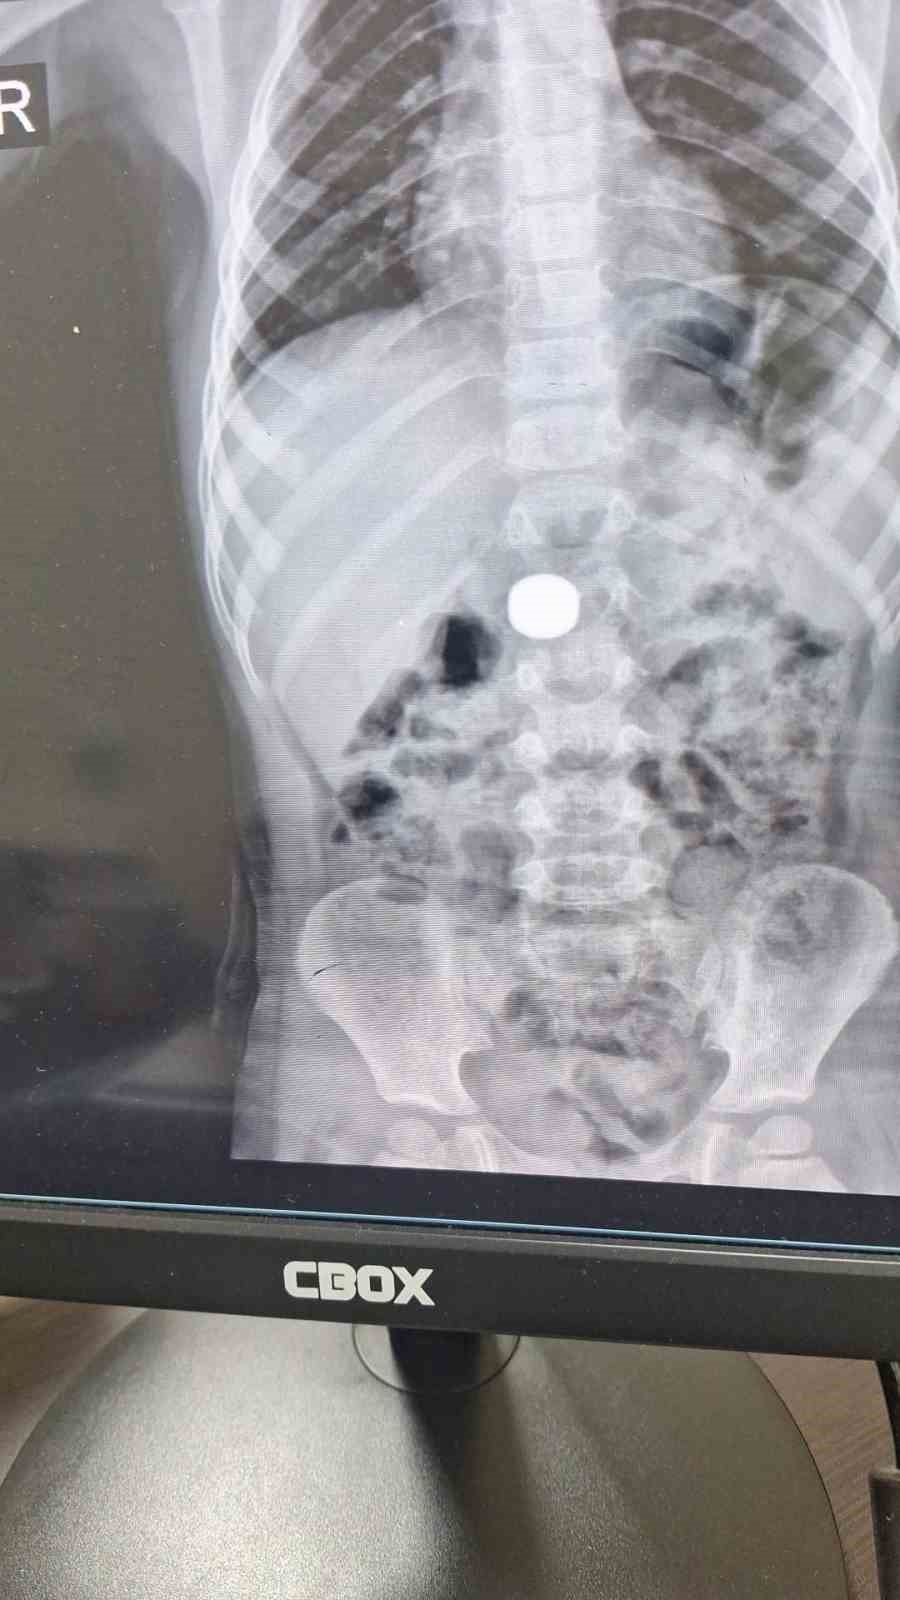

Karaman’da yuttuğu iki mıknatıs nedeniyle bağırsak tıkanıklığı yaşayan çocuk, ameliyatla sağlığına kavuştu.

Karaman’da 4 yaşındaki İ.K.’nin mıknatıs yuttuğundan şüphelenen ailesi, Karaman Eğitim ve Araştırma Hastanesi Acil Servisi’ne başvurdu. Yapılan tetkiklerde çocuğun ince bağırsağında iki adet mıknatıs bulunduğu tespit edildi. Gözlem altına alınan çocuğun sağlık durumu 5 gün boyunca takip edildi. Çocuk Cerrahisi Uzmanı Doç. Dr. Mehmet Uysal’ın gerçekleştirdiği operasyonla bağırsakta tıkanıklığa yol açan iki mıknatıs başarılı bir şekilde çıkarıldı.

Hastayı 5 gün boyunca takibe aldıklarını belirten Doç. Dr. Mehmet Uysal, gözetim süresince çekilen filmlerde mıknatısların yer değiştirmediğini söyledi. Uysal, "Hastayı genel anestezi altında ameliyata aldık. İnce bağırsakta iki mıknatısın birbirine yapışık halde olduğunu gördük. Gerçekleştirdiğimiz operasyonla mıknatısları çıkardık. Ameliyat sonrası hastamız üçüncü gününde taburcu edildi. Şu an genel durumu iyi" dedi.